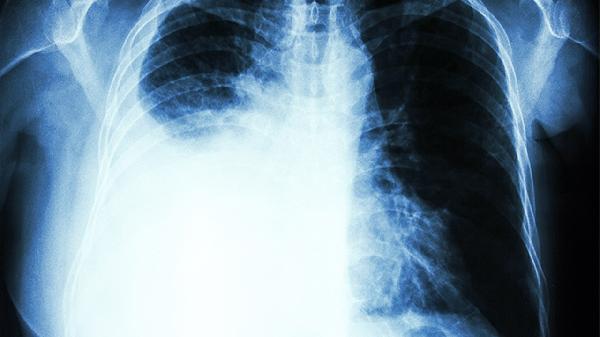

如果同时出现手指麻木、腋下淋巴结肿大,或者疼痛沿着手臂内侧放射,建议尽快做胸部CT排查。长期吸烟者出现不明原因肩痛,更要提高警惕。

若无感冒、用嗓过度等情况,声音嘶哑持续两周不缓解,特别是伴随饮水呛咳时,建议进行支气管镜检查。